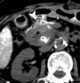

Pancreatic cancer metastasis

Metastasis is a pathogenic agent's spread from an initial or primary site to a different or secondary site within the host's body; the term is typically used when referring to metastasis by a cancerous tumor. The newly pathological sites, then, are metastases (mets). [Source: Wikipedia ]